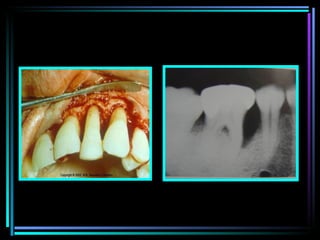

EXTENSION OF GINGIVAL INFLAMMATION The most common cause of bone destruction in periodontal disease is extension of inflammation from the marginal gingiva into the supporting PD tissue. Periodontitis  is always preceded by gingivitis, but not all gingivitis progresses to periodontitis The transition from gingivitis to periodontitis is associated with changes in composition of bacterial plaque.

The recurrence of episode of acute destruction over time may be one mechanism leading to progressive bone loss in marginal gingivitis. The extension of inflammation is modified by pathogenic potential of plaque or resistance of host Degree of fibrosis of gingiva Width of attached gingiva Peripheral reactive fibrogenesis and osteogenesis . “ walling off “ by fibrin-fibrinolytic system.

Histopathology

After inflammation reaches the bone by extension from the gingiva,it spreads into the marrow spaces  And replaces the marrow with leukocytic and fluid exudate,new blood vessel, & proliferating fibroblasts. Multinuclear osteoclasts and mononuclear phagocytes increase in number ,the bone surfaces appear ,lined with howship’s lacunae.

In marrow spaces ,resorption proceeds, causing a thinning of surrounding bony trabeculae and enlargement of marrow spaces  Destruction of bone  and reduction in height

Radius of action 1.5 to 2.5 mm within which bacterial plaque induce loss of bone. Interproximal angular defect can appear in spaces that are wider than 2.5 mm because bone marrow spaces would be destroyed entirely.